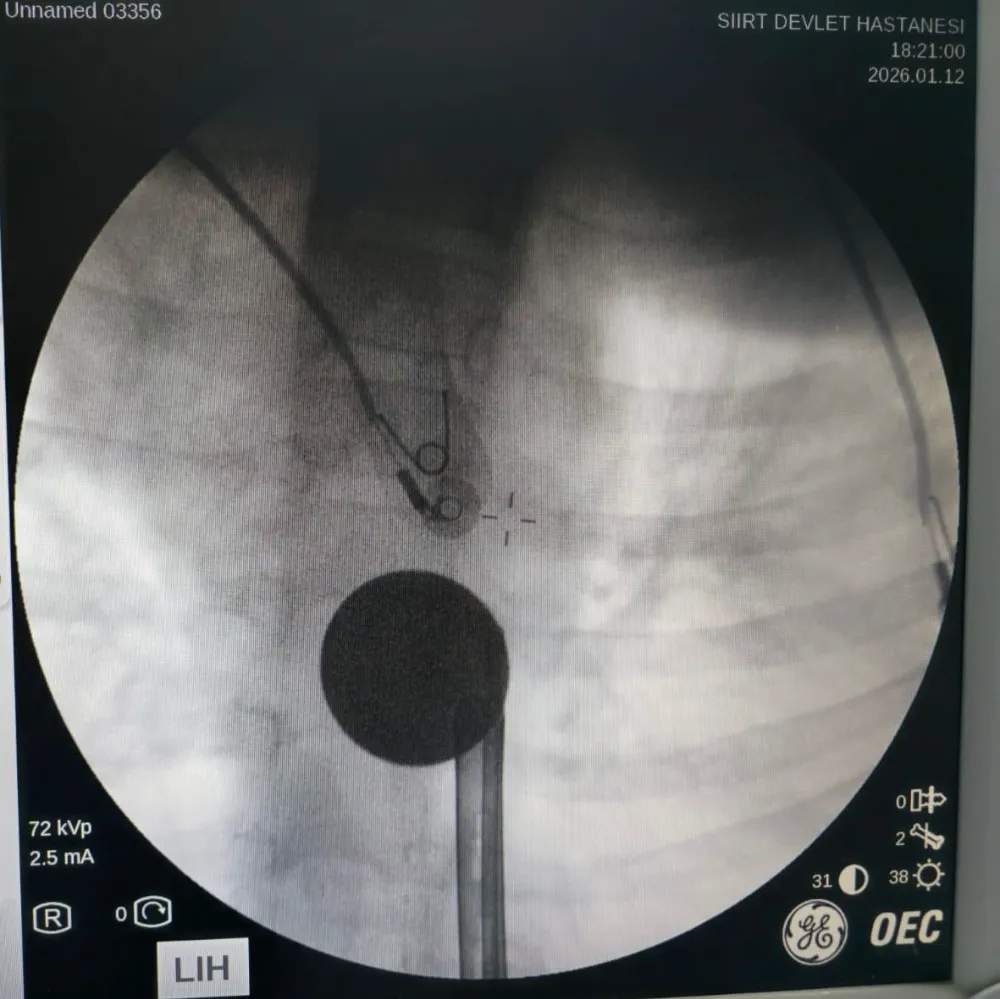

Yabancı cisim yutma şikayetiyle ailesi tarafından Siirt Eğitim ve Araştırma Hastanesine getirilen 8 yaşındaki Y.K., yapılan ilk değerlendirme ve görüntüleme tetkiklerinin ardından ilgili branşlarca operasyona alındı. Y.K.'nın yemek borusuna kadar ilerlediği tespit edilen madeni para, gastroenteroloji uzmanı Dr. Yaren Dirik ve kulak burun boğaz hekimi Yasin Gökçınar tarafından müdahale edilerek çıkartıldı. Operasyonun ardından bir süre gözlem altında tutulan Y.K., tedavisinin tamamlanmasıyla taburcu edildi.

Siirt Eğitim ve Araştırma Hastanesi Başhekim Yardımcısı Uzman Dr. Burak Özkan, çocuk hastalarda yabancı cisim yutma vakalarının ciddi riskler oluşturabileceğini söyledi. Uzm. Dr. Özkan, "Hastanemize başvuran 8 yaşındaki hastamızın yemek borusuna kaçan madeni para, gastroenteroloji ve KBB ekiplerimizin koordineli ve titiz çalışmasıyla herhangi bir komplikasyona yol açmadan başarılı bir şekilde çıkarılmıştır. Operasyon süreci sorunsuz geçmiş olup hastamızın genel durumu iyidir" dedi.